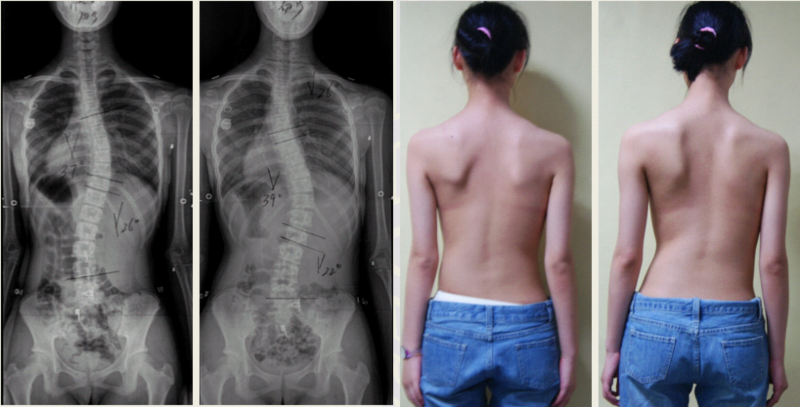

青少年特发性脊柱侧凸(adolescent idiopathic scoliosis, AIS)是一种病因至今未明的三维畸形,发病率约为2%-4%,目前全世界有逾千万AIS患者。作为全球最大的脊柱侧凸矫形中心,鼓楼医院脊柱外科已成功为数千位AIS患者进行手术矫形。为进一步探索AIS病因学基础,邱勇教授带领的研究团队收集了中国长江流域及香港地区总计4317例AIS患者以及6016例正常对照者DNA(为目前全球已知最大的AIS组织样本库),首次利用全基因组芯片技术定位了4个与汉族AIS发病相关的易感基因,包括1p36.32 AJAP1,2q36.1 PAX3,18q21.33 BCL-2和10q24.32 LBX1AS1。上述基因分别与肌肉、软骨发育及细胞凋亡等通路相关,从而为AIS病因学提供了新的线索,并为未来AIS个体化诊疗提供理论基础。